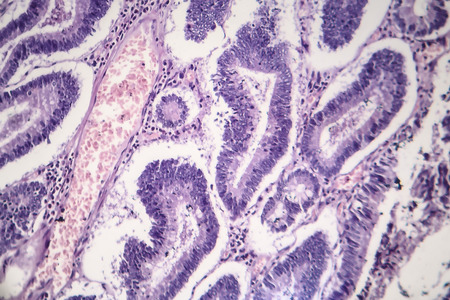

Intestinal polypoid adenoma, light micrograph, photo under microscope